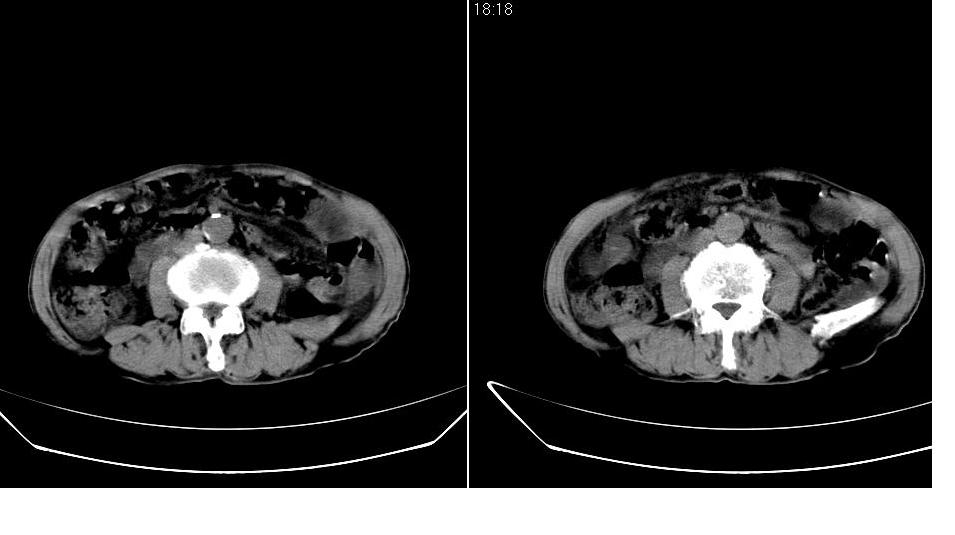

男,76岁,上腹部疼二天来就诊,彩超提示肝左叶占位,随后做上腹部ct平扫,今天做上腹部ct增强扫描,手工推药,效果不好,请谅解。

肝左叶s4肿块强化形式大概是:慢进慢出,逐渐强化----考虑血管瘤/腺瘤?{动脉期应更提前扫}。

1)肝右叶前段低密度灶,不排除肝癌可能;建议查afp。2)右肾上极囊肿。

肝内胆管积气扩张,胆囊增大,肝右前叶低密度灶,逐渐强化,一元论,胆系感染,局限性肝脓肿;右肾囊肿。

考虑肝s4段肝脓肿可能?未排除肝癌。右肾上极囊肿。